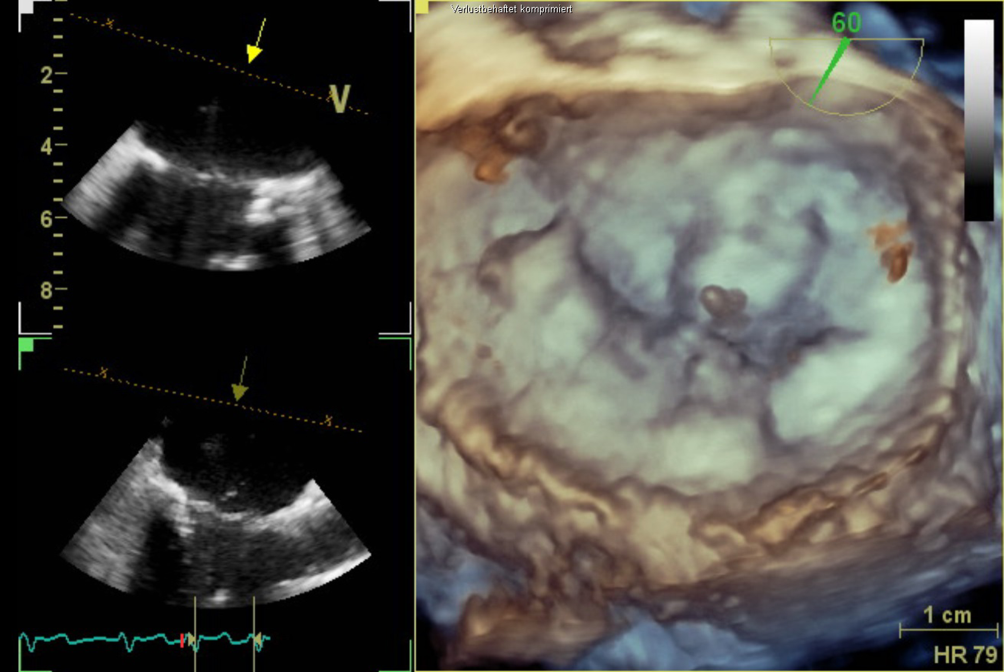

Abb. 1

Transösophageale Echokardiographie. 3‑D-Ansicht mit Aufsicht auf die Mitralklappe. Zu sehen ist der Sehnenfadenabriss im Segment P2

Bild vergrößern

Abb. 3

Transösophageale Echokardiographie. 3‑D-Ansicht mit Aufsicht auf die Mitralklappe. Zu sehen ist das PASCAL-Device (Edwards Lifesciences) zwischen den Segmenten A2 und P2